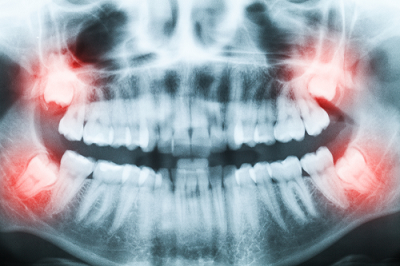

Οι 3οι γομφίοι (φρονιμήτες) ολοκληρώνουν την διάπλαση τους και ανατέλλουν στη στοματική κοιλότητα στην ηλικία των 18-24 ετών, ενώ σε κάποιες περιπτώσεις, μπορεί να συνεχίσουν και σε μεγαλύτερη ηλικία. Είναι τα τελευταία δόντια που ανατέλλουν στο στόμα και παρουσιάζουν μεγάλη ποικιλία ως προς την μορφολογία τους και την φορά ανατολής τους. Πολύ συχνά, στην περιοχή όπου φυσιολογικά προβάλλουν οι 3οι γομφίοι, έχουμε έλλειψη χώρου, γεγονός που οδηγεί στην έγκλειση του δοντιού και τη μη ανατολή του στη στοματική κοιλότητα. Ανάλογα με τη θέση που βρίσκονται, προκαλούν και αντίστοιχα προβλήματα. Το πιο συνηθισμένο πρόβλημα είναι η, λόγω θέσης, ανεπαρκής υγεινή της περιοχής, κάτι που αναπόφευκτα οδηγεί στην μόλυνση και φλεγμονή (περιστεφανίτιδα) και στην ανάπτυξη πόνου, ερυθρότητας, καθώς και γενικότερων συμπτωμάτων, όπως πόνος στο αυτί, στον λαιμό και στο κεφάλι. Ειδικά στην περίπτωση όπου τμήμα της μύλης του δοντιού έχει εμφανιστεί (σε αυτή την περίπτωση ο φρονιμήτης ονομάζεται ημιέγκλειστος), η κατακράτηση τροφών και μικροβίων είναι ευκολότερη και η εμφάνιση περιστεφανίτιδας πιο πιθανή.

Στην περίπτωση που η φορά του δοντιού δεν είναι προς το μασητικό επίπεδο, αλλά έρχεται προς τα εγγύς, μπορεί να προκαλέσει τοπικά προβλήματα στον 2ο γομφίο, τα οποία είναι ο τερηδονισμός του, αλλά και η καταστροφή του οστού που τον στηρίζει, με αποτέλεσμα την μακροπρόθεσμη εμφάνιση προβλήματος. Σε πολλές περιπτώσεις, η προς τα εμπρός κλίση του φρονιμήτη προκαλεί ''σπρώξιμο΄΄των δοντιών, με αποτέλεσμα να εμφανιστεί συνωστισμός, ειδικά στην πρόσθια περιοχή, οπότε προβαίνουμε σε προληπτική αφαίρεσή του.